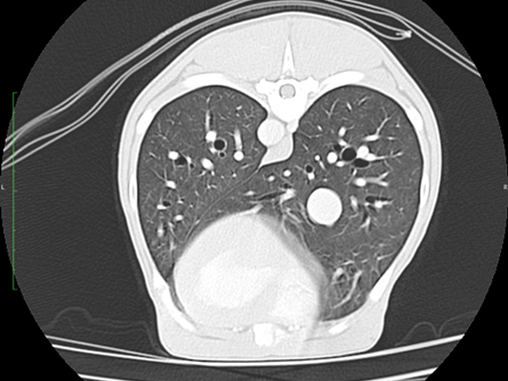

Because the technique uses a very fine beam of Xrays detected by a fine array of sensors a 3D picture can be built up of the subject being examined. There are three types of CT, helical, linear and cone beam, helical and linear provide the greatest image quality allowing detailed imaging of patients as large as a Great Dane’s chest to as small as a kitten’s foot.

The inherent contrast afforded by the differences between, air, bone, fat and soft tissue is also enhanced by the use of Iodinated intravenous or intra arterial contrast (intravenous being the most common) and so very fine detail of tomography, internal architecture and vascular supply and drainage is possible for bones, the abdomen, the chest, head and neck in fact almost every body part. Only brain, spinal cord and muscular tendinous injuries are areas where MRI may provide superior imaging.